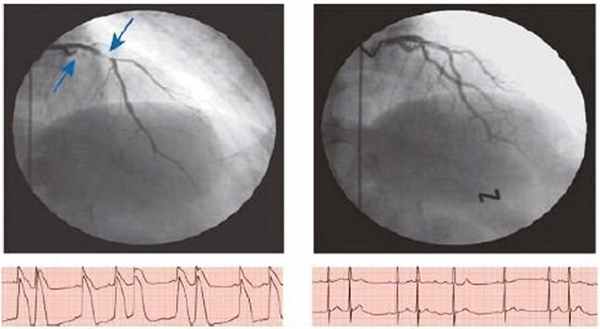

После введения эргометрина наблюдается выраженный спазм проксимальной части передней межжелудочковой ветви (ПМЖВ) левой коронарной артерии – динамическая окклюзия (рис.).

Причины развития такого спазма недостаточно выяснены. Ангиографические исследования 60-х годов показали, что ВВС имеет уникальный механизм, заключающийся в спазме (до состояния окклюзии/субокклюзии) эпикардиальной артерии, приводящем к кратковременной трансмуральной ишемии. На ЭКГ во время спазма КА обычно регистрируется элевация сегмента ST, при КАГ — локальный окклюзирующий спазм (по А. Кэмм и соавт., 2011) [7] (рис. 2).

Рис. 2. (по A. Camm и соавт., 2011). Документальное подтверждение окклюзирующего коронарного вазоспазма обеих ветвей левой КА (передней нисходящей и огибающей артерий; показано стрелками) после внутрикоронарного введения эргоновина пациенту с типичной ВСС (наверху слева). Коронарный вазоспазм быстро купирован после внутрикоронарного введения изосорбида динитрата (наверху справа). ВСС может сопровождаться угрожающими нарушениями ритма (желудочковая тахикардия, фибрилляция желудочков), изредка приводить к развитию ИМ и даже к внезапной смерти. Нитраты обычно купируют приступ в течение нескольких минут [8]. Известно, что при нормальных обстоятельствах эпикардиальные коронарные артерии вносят не более чем 10% вклад в коронарное сопротивление и регуляцию перфузии миокарда. Это может быть обусловлено как низким уровнем мышечного тонуса в эпикардиальных артериях, так и влиянием эндотелия, который ослабляет вазоконстрикторные сигналы и усиливает сосудорасширяющую способность. Однако, когда эндотелий поврежден, нарушение эндотелиальной функции в сочетании с повышением реактивности гладкомышечных клеток (ГМК) приводит к изменению реакции КА на регулирующие их тонус воздействия с усилением констриктивного компонента, в результате чего и происходит коронарный вазоспазм. Подобные нарушения возникают даже при небольшой выраженности атеросклероза. Как правило, спазм КА происходит локально в эпикардиальной артерии, но могут спазмироваться сразу несколько сегментов одной артерии или несколько КА, что может привести к преходящей трансмуральной ишемии миокарда даже при малоизмененных коронарных артериях. Считается, что гиперреактивность ГМК эпикардиальных КА является основным субстратом для коронарного вазоспазма. Во время спазма происходит радиальная перестройка ГМК, что приводит к медиальному утолщению средней оболочки артерии и образованию складчатости, создавая эффект поршня, приводящего к сужению просвета сосуда [9, 10]. В дополнение к указанной гиперреактивности снижение биодоступности оксида азота (NO) также играет важную роль в развитии коронарного спазма. Это связано с тем, что NO подавляет эндотелиальное производство эндотелина I и ангиотензина II, которые являются мощными вазоконстрикторами, а также активируют пролиферацию клеток гладких мышц. Таким образом, основными звеньями патофизиологии коронарного вазоспазма являются эндотелиальная дисфункция, которая может быть обусловлена окислительным стрессом, генетическими факторами или воспалением. Также играет роль усиление активности симпатической нервной системы, например в результате увеличенного выброса катехоламинов, связанного с интенсивными физическими нагрузками, эмоциональным стрессом, воздействием сильного холода [11]. Спонтанный спазм КА при КАГ у больных с предполагаемой ВСС наблюдают редко. Среди известных провоцирующих факторов развития ВСС — холод, курение, выраженные нарушения электролитного обмена, гипервентиляция, употребление кокаина, алкалоидов спорыньи, аутоиммунные заболевания. В связи с этим для подтверждения наличия вазоспазма часто используют провокационные пробы. Гипервентиляция и холодовая проба характеризуются низкой чувствительностью в диагностике коронароспазма, в настоящее время применяются редко. Большей диагностической ценностью обладают пробы с ацетилхолином и эргоновином (рис. 2). Поскольку при внутривенном введении эргоновина возможны летальные осложнения (из-за пролонгированного спазма нескольких сосудов), предпочтительнее его внутрикоронарное введение. В настоящее время в большинстве клиник для провокации вазоспазма широко используется интракоронарное введение ацетилхолина или эргоновина. Последнее не рекомендуется пациентам с неизученной коронарной анатомией и значительными стенозами коронарных артерий [12].